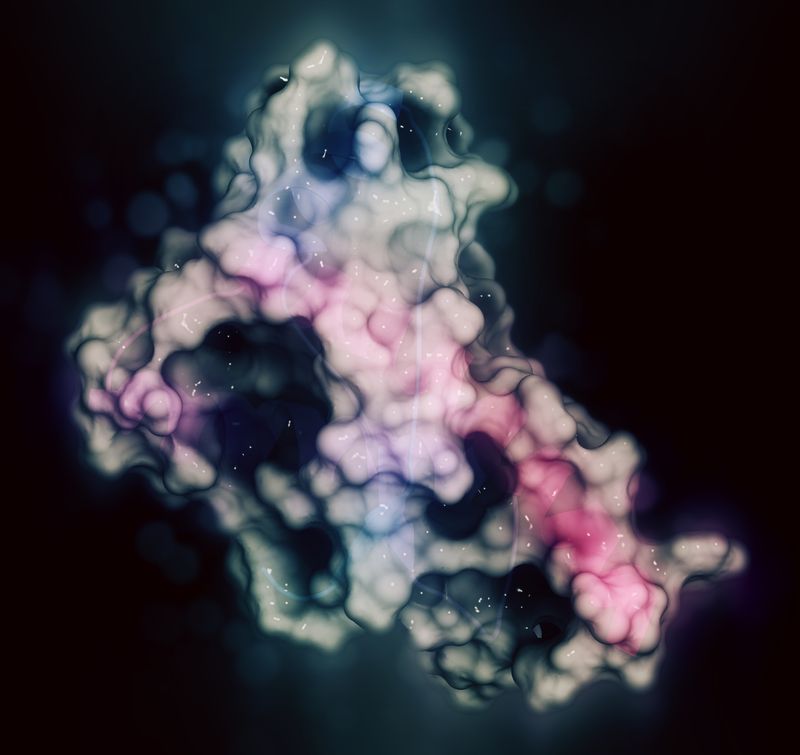

The rest of this article is behind a paywall. Please sign in or subscribe to access the full content.Her death was not caused by a bacteria, a fungus, a virus, a parasite, or some kind of chemical agent, but through exposure to prions: a misfolded infectious protein that can trigger typical proteins in the brain to fold abnormally.

Surprisingly little is known about prion diseases, although scientists do know they arise when certain proteins found on many types of cells begin to misfold in the brain. These misfolded prions can run amok by changing the shape of other neighboring proteins, which go on to become misfolded prions, further spreading the “damage”. Unlike other infectious agents, such as bacteria, fungi, or a virus, they do not contain any DNA or its relative RNA.